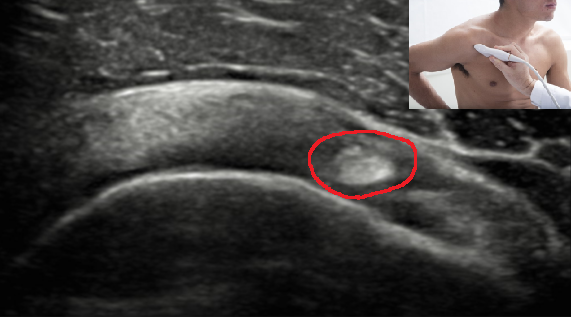

QUAL A ESTRUTURA ASSINALADA NA FIGURA?

PORÇÃO INTRA ARTICULAR DO TENDÃO DA CABEÇA LONGA DO BÍCEPS BRAQUIAL